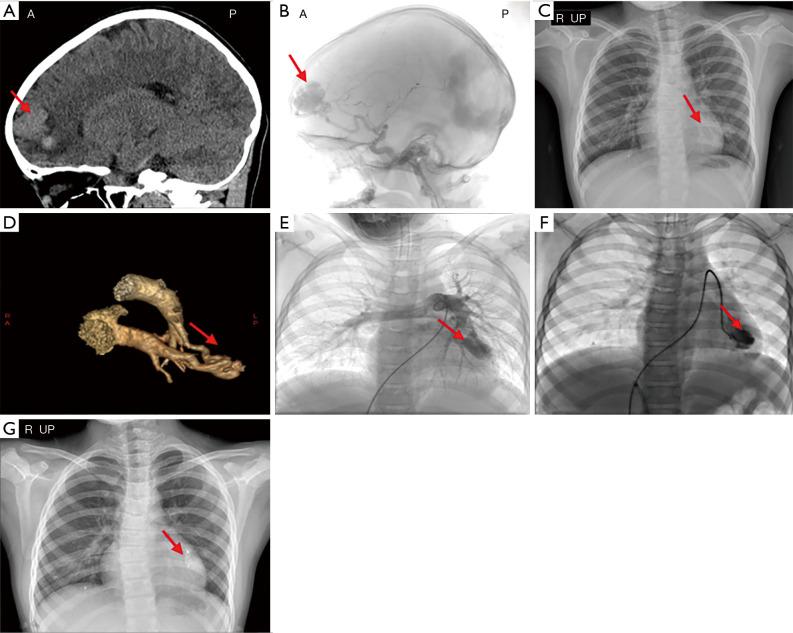

Hereditary hemorrhagic telangiectasis (HHT) is an autosomal dominant vascular disease, and approximately 80% of all HHT cases are caused by gene mutation. In this report, we analyzed the case of an 11-year-old girl who had intracranial bleeding when she was 7 years old. Her brain computed tomography (CT) scans and craniocerebral angiography results revealed that she had multiple cerebral arteriovenous malformations (CAVMs). Cardiac computed tomography angiography (CTA) revealed a pulmonary arteriovenous malformation (PAVM) located in a segment of the left lung. This patient's primary diagnosis was of CAVMs and PAVMs. Both cerebral vascular embolization therapy and interventional treatment for PAVMs were performed to treat these respective conditions. The operations were successful and the patient's prognosis was good. To confirm the patient's diagnosis and the cause of her conditions, peripheral blood was collected from her and her family for whole-exome sequencing (WES). Sanger sequencing was used to verify these results and STRUM software was used to predict the presence of mutant proteins. We found a new mutation of the endoglin (ENG) gene present in this family; this mutation is known as c.1466del (p.Gln489Argfs2). The patient's mother was a carrier of this heterozygous mutation. STRUM software confirmed that the configuration of the ENG protein p.Gln489Argfs2 site changed with this mutation. We believe this c.1466del (p.Gln489Argfs2) mutation affects ENG protein function, and the resultant ENG protein dysfunction leads to HHT. When a child has multiple vascular malformation, HHT should be considered as a primary diagnosis.

遗传性出血性毛细血管扩张症(HHT)是一种常染色体显性血管疾病,所有HHT病例中约80%由基因突变引起。在本报告中,我们分析了一名11岁女孩的病例,她7岁时发生颅内出血。她的脑部计算机断层扫描(CT)和脑血管造影结果显示,她患有多处脑动静脉畸形(CAVM)。心脏计算机断层扫描血管造影(CTA)显示左肺一段有肺动静脉畸形(PAVM)。该患者的初步诊断为CAVM和PAVM。分别对这些病症进行了脑血管栓塞治疗和PAVM介入治疗。手术成功,患者预后良好。为了确诊患者的病情及其病因,采集了她及其家人的外周血进行全外显子组测序(WES)。使用桑格测序法验证这些结果,并使用STRUM软件预测突变蛋白的存在。我们在这个家族中发现了内皮糖蛋白(ENG)基因的一个新突变;这个突变被称为c.1466del(p.Gln489Argfs2)。患者的母亲是这种杂合突变的携带者。STRUM软件证实,ENG蛋白p.Gln489Argfs2位点的结构因该突变而改变。我们认为这种c.1466del(p.Gln489Argfs2)突变影响ENG蛋白功能,由此产生的ENG蛋白功能障碍导致了HHT。当儿童患有多处血管畸形时,应将HHT作为初步诊断。